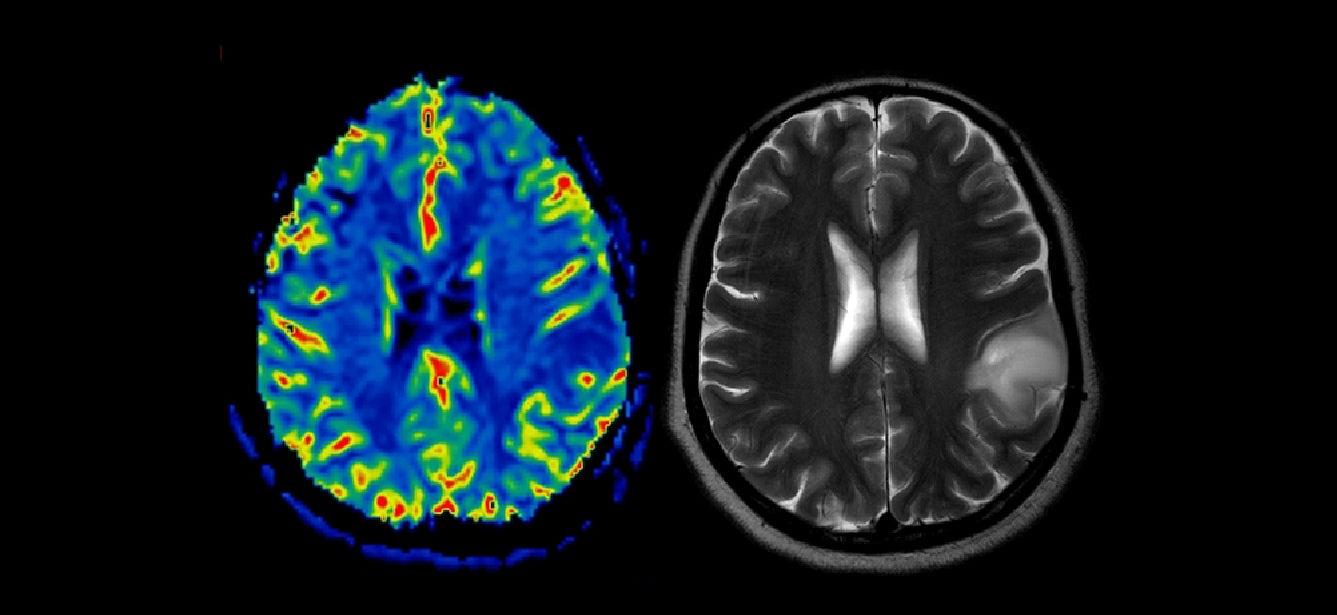

Brain Health

How Does Precision Health Support Healthy Aging?